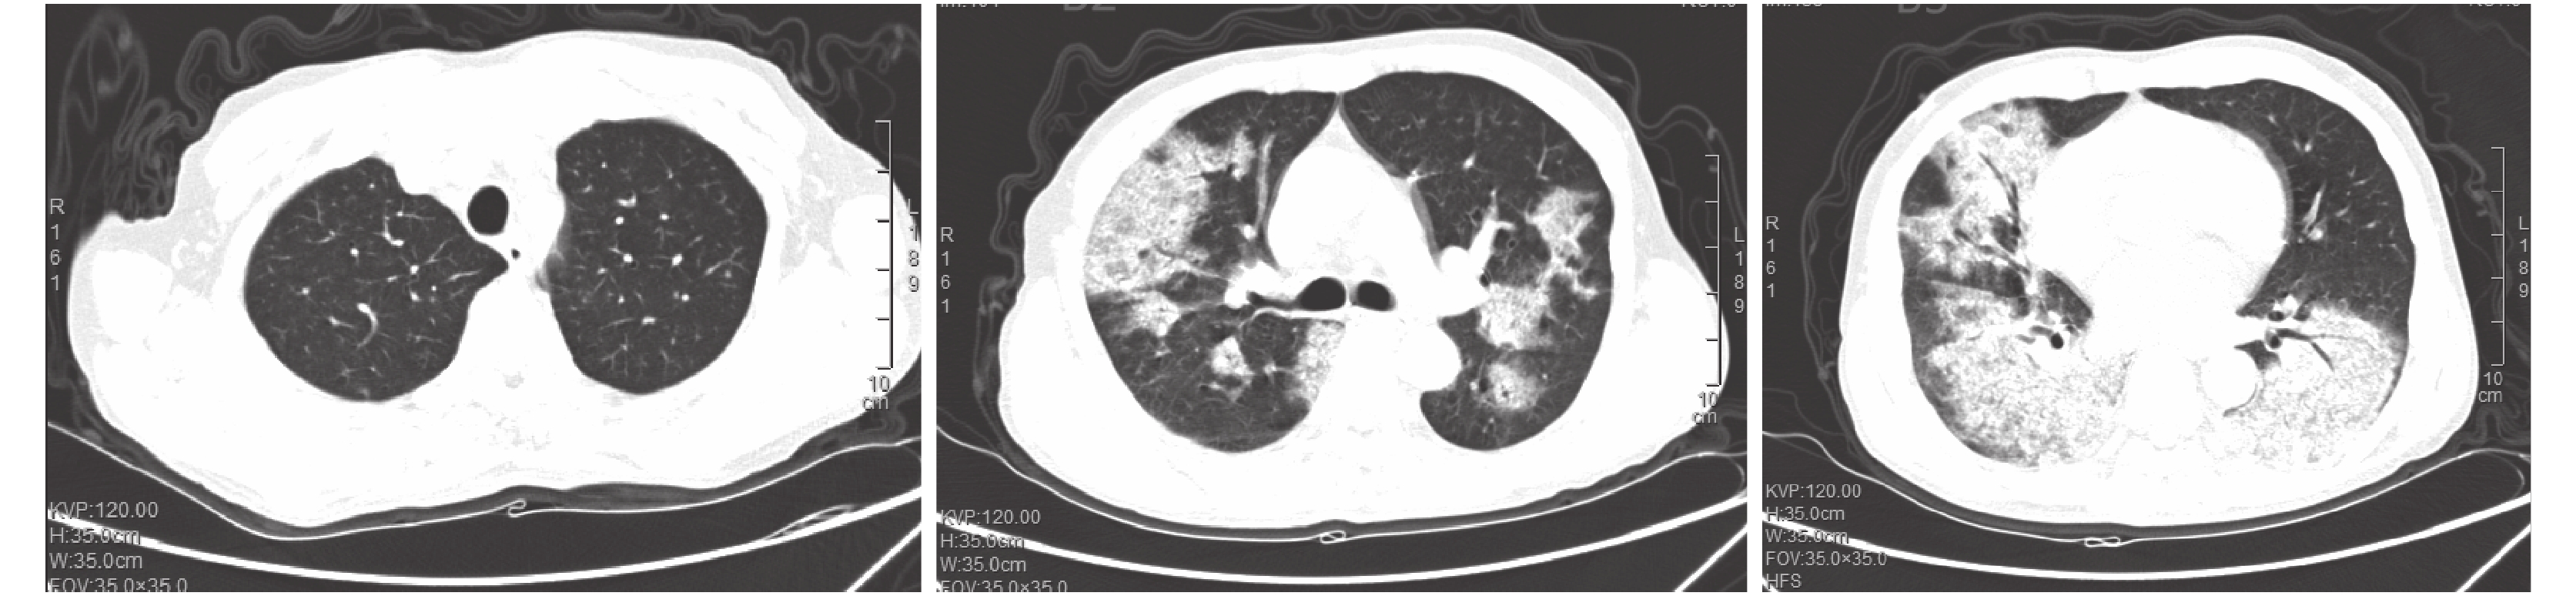

圖3

2017 年 3 月 19 日胸部 CT 檢查像

兩肺見團片狀不均勻實變影,其間見空氣支氣管征,所見各支氣管通暢

結合臨床表現和影像學(圖 3),考慮肺部繼發性真菌感染,不能完全排外合并淋巴瘤肺浸潤可能。征得家屬同意后,予以米卡芬凈抗真菌治療,并行經皮肺穿刺活檢。活檢病理(圖 4)提示肺泡上皮增生,肺泡間隔增寬,血管擴張,慢性炎細胞浸潤,肺泡腔內見纖維素性栓子,考慮機化性肺炎;特殊染色:PAS(–)、PASM(–)、抗酸染色(–)。綜合臨床表現、影像及病理,病變符合 AFOP 的診斷。活檢后立即給予甲基潑尼松龍40 mg/d。患者呼吸困難逐漸好轉體溫降至正常,血氣分析恢復正常。1 周后復查胸部 CT 提示病變較前明顯好轉。出院后使用甲基潑尼松龍 40 mg/d 維持治療。出院后 4 周復查胸部 CT 示病灶明顯吸收(圖 5)。隨訪至撰稿日,患者未見復發。

診斷 AFOP 具有一定的挑戰性。影像學表現常不具備特異性,且表現多樣,最常表現為累及雙肺的彌漫浸潤性病變,呈雙肺彌漫斑片狀實變陰影改變,雙側肺底多見,也可見單側結節狀實變陰影[2]。AFOP 容易與其他肺部疾病混淆(如肺水腫、感染性肺炎、肺部淋巴瘤等)[8]。急性起病的 AFOP 影像學表現類似于 DAD,包括集中于雙肺基底部的彌漫性磨玻璃影。而亞急性起病患者的影像學表現類似 OP,包括局灶性和彌漫性肺實變[9]。本例患者即為亞急性起病,肺部 CT 可見雙肺彌漫性磨玻璃影演變為肺實變。